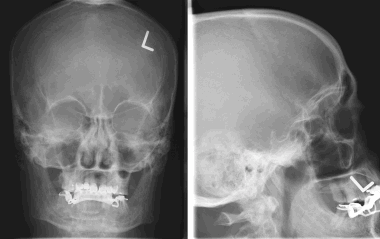

(Слева) КТ в костном окне, аксиальная проекция. Характерные инфильтративно-склеротические костные изменения в области основания черепа и яремного отверстия. Обратите внимание, что внутричерепная часть опухоли частично кальцифицирована.

8. На рентгеновском снимке во фронтальной плоскости хорошо заметно кальцифицированное образование в области лобной пазухи. На снимке в латеральной проекции образование визуализируется кверху от решетчатой пластинки. Несмотря на то, что по результатам исследования можно заподозрить, обнаруженные признаки неспецифичны, и поэтому обнаруженное внутричерепное образование требует дообследования при помощи КТ.

Большинство рентгеновских снимков не отображают признаков наличия заболевания. Менингиомы типа en plaque характеризуются диффузным гиперостозом, чаще в области крыла клиновидной кости и птериона. Такие результаты исследования с большой долей вероятности свидетельствуют о наличии

болезни.